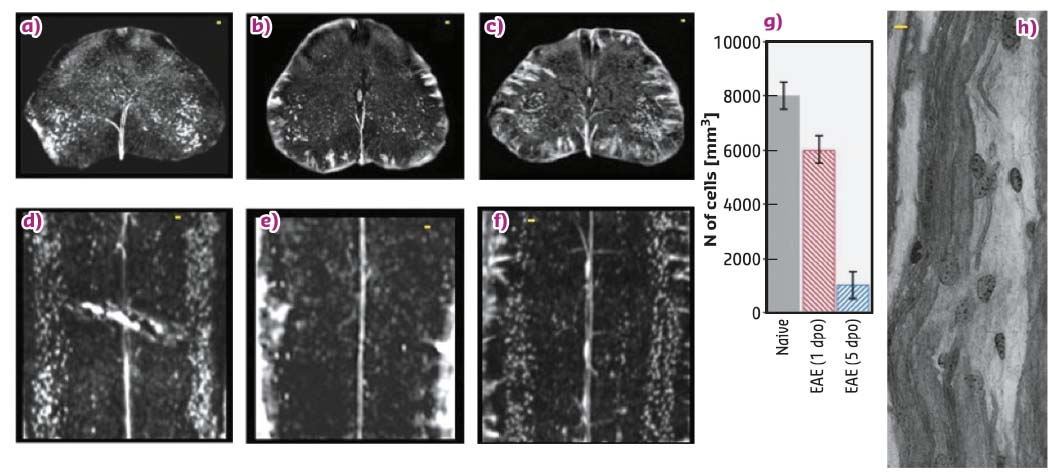

Simultaneous 3D XPCT imaging of neuronal alterations during EAE (Figure 69) supports the findings [2] of a massive loss of lower motor neurons in multiple sclerosis patients and in mouse EAE from early disease stages, with evidence of apoptotic neuronal death. The data suggest that the angiogenesis detected at the acute phase of EAE, by 2D immunohistochemical analysis of tissue slices, is in fact not efficient, and that the massive loss of neurons observed reflects the demonstration of pyknotic neurons in EAE observed by 2D techniques.

Fig. 69: Effect of MSC treatment on the altered neuronal network in EAE (a-g), scale-bar 20 µm. Nano-XPCT (scale-bar 8 µm) of myelin damage in EAE (h). |